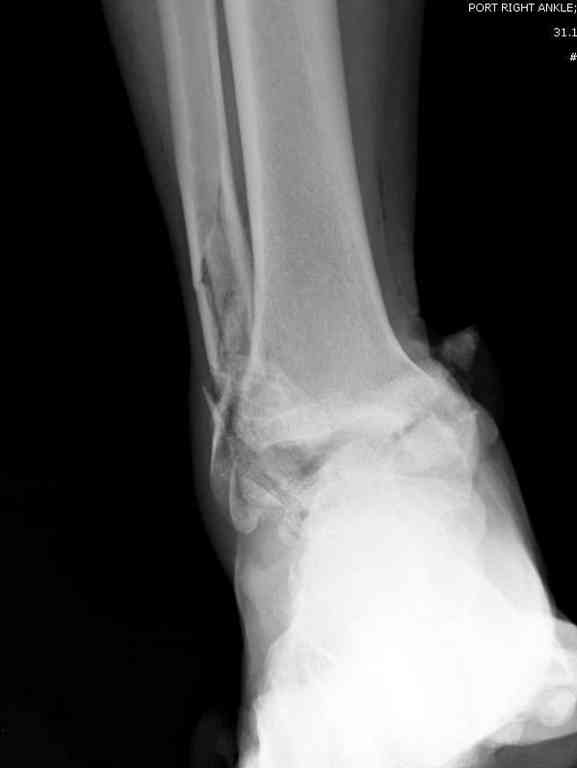

Прошу коллег помочь советом.3 дня назад поступила пациентка 23 года с переломом шейки ладьевидной справа, переломом лодыжек и заднего края б/берцовой кости со смещением и подвывихом кзади, переломом внутреннего мыщелка правого бедра без смещения. Дежурными хирургами проведена репозиция в левом г/ст суставе успешная, попытка репозиции таранной кости ухудшило положение отломков. Планируем провести повторную репозицию и фиксацию винтами. 1. Закрытая репозиция рентгенконтоль интраоперационный (аппарат Арман) ификсация из заднее-наружного доступа. 2. При неудачной закрытой репозиции переходим на открытое вправление двумя доступами медиальным и латеральным "по ходу оси таранной кости" и через дополнительный задний доступ вводим винты кортикальные 4,5 мм или 3,5 мм 3. после открытой репозиции фиксация двумя винтами через боковые доступы погружая их под суставную поверхность Сергей Зырянов ЦРБ Новосибирская область

Переломовывих тарана с повреждением медиальной стороны. Через 4 часа после поступления проведена репозиция и фиксация тарана после Irrigation&Debridment. Частичное несращение медиальной лодыжки не беспокоит, вернулся к активному образу жизни. Полная нагрузка разрешена через 11 недель. Финальные снимки через 11 месяцев.